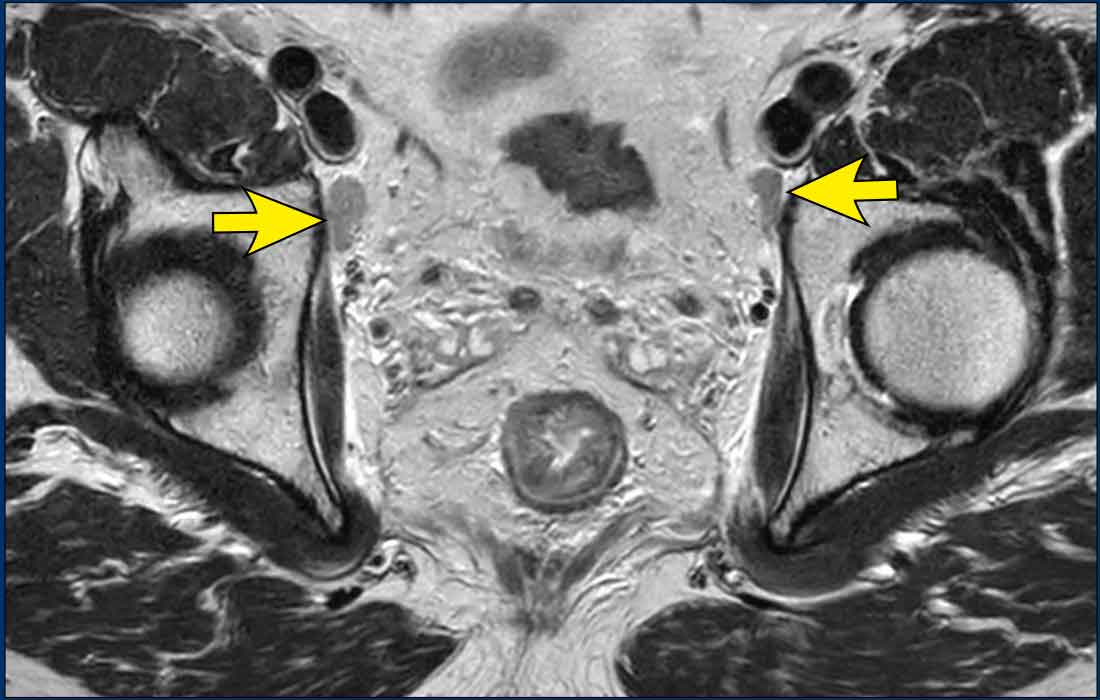

Tumor deposits and EMVI

Tumor deposits are strongly associated with EMVI, often considered a continuation of vascular tumor spread—beginning with EMVI and progressing to tumor deposits in advanced disease [ref]

MRI data show that tumor deposits co-occur with EMVI in up to 80% of cases [ref].

Image Example

• White arrows: EMVI—tumor signal extending into adjacent vessels, with vessel expansion and contour disruption.

• Black circles: Tumor deposits seeded along the vessels.